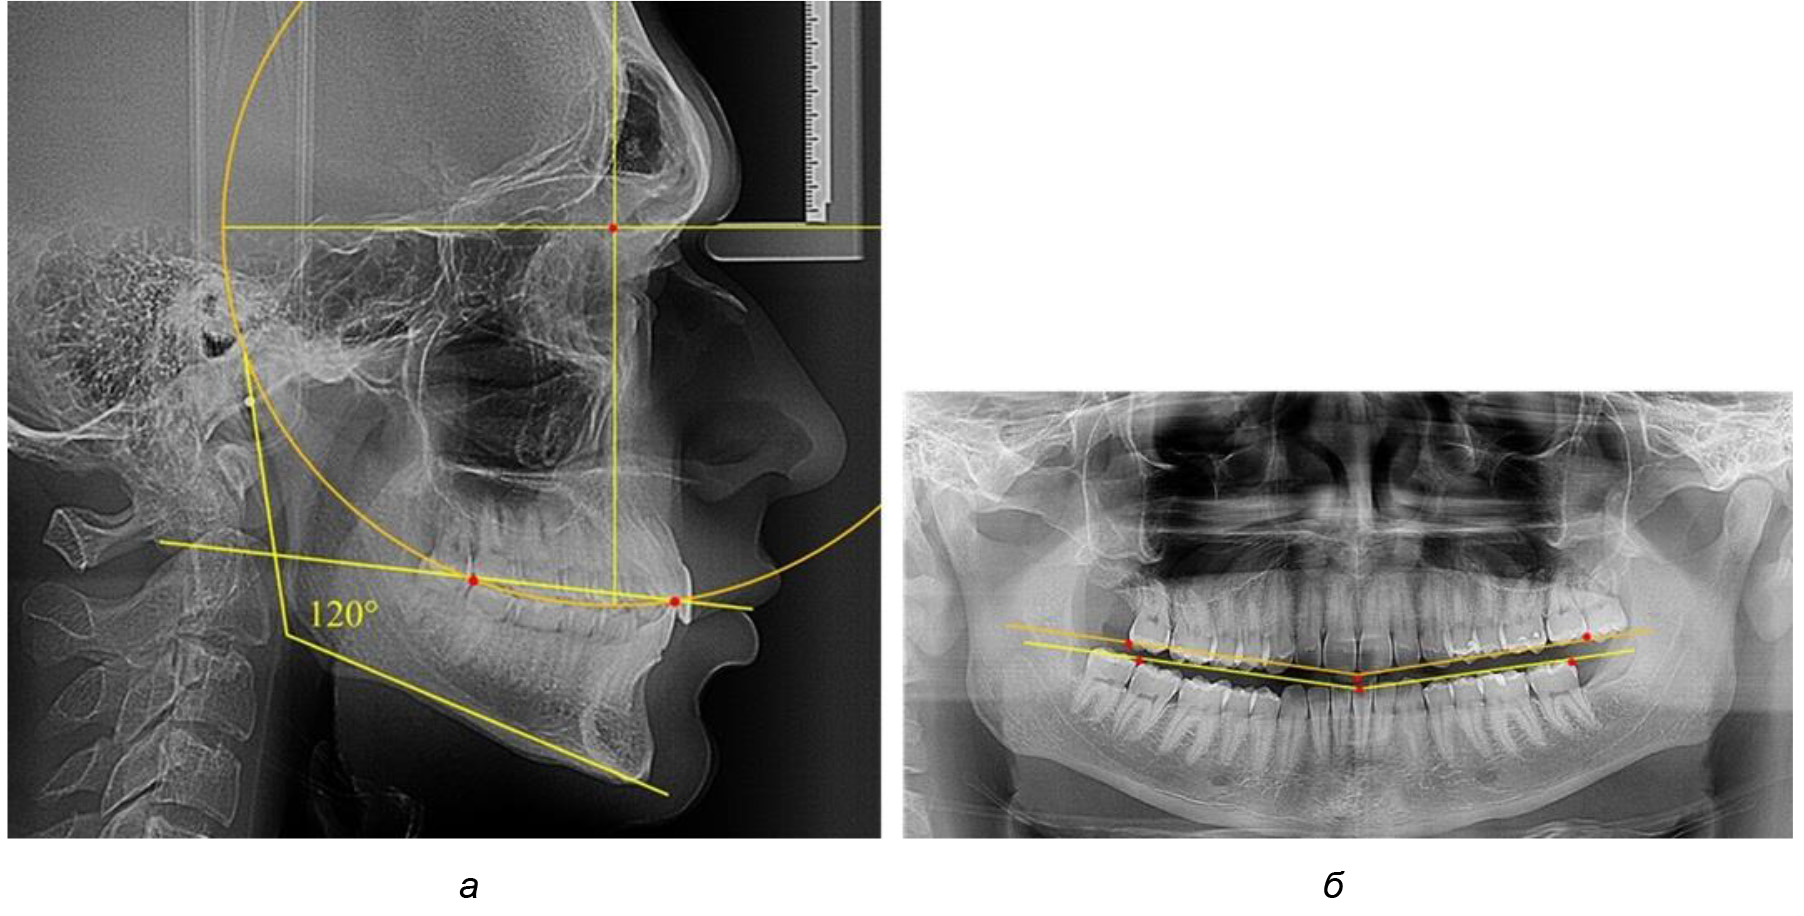

У людей с аномалиями окклюзии по сагиттали в 1-й подгруппе обследовано 9 человек. Обращает на себя внимание увеличение глубины кривой Spee, что нами расценивалось, как патологическая форма кривой линии окклюзии.

Глубина кривой Spee в среднем по 2-й подгруппе составила (5,69 ± 1,57) мм, что было достоверно больше, чем у людей с физиологической окклюзией (р ˂ 0,05). Достоверных различий с показателями, полученными при анализе ТРГ и ОПТГ, нами не отмечено (р ˃ 0,05). Отношение радиуса окружности к сагиттальному размеру окклюзионной линии в среднем по подгруппе составляло 1,372 ± 0,042 и не соответствовало числу Фибоначчи, что может быть использовано в качестве диагностического критерия определения патологической формы кривой Spee. После лечения пациентов техникой «прямой» дуги было отмечено незначительное увеличение сагиттального размера окклюзионной лини в среднем на (2,12 ± 0,77) мм. Однако окклюзионная линия практически касалась окклюзионного контура всех жевательных зубов, и отмечалось практически полное отсутствие кривой Spee.

Таким образом, проведенное лечение техникой «прямой» дуги способствует нормализации окклюзионного равновесия и торку передних зубов, однако не соответствует оптимальному окклюзионному статусу, характеризующему физиологическую окклюзию. При этом величина нижнечелюстного угла оставалась на прежнем уровне (рис. 5).

Рис. 5. Особенности ТРГ при патологической кривой Spee до лечения (а) и после лечения (б) техникой «прямой» дуги

Во 2-й подгруппе 2-й группы было обследовано 7 человек.

Указанная величина не имела достоверного отличия с 1-й подгруппой (р ˃ 0,05), что определяло однородность групп по количественному признаку.

Обращает на себя внимание, что глубина кривой Spee в анализируемой подгруппе практически не отличалась от показателей, полученных у людей с физиологической окклюзией, и составляла (4,23 ± 1,58) мм. Отношение радиуса окружности к сагиттальному размеру окклюзионной линии в среднем по подгруппе составляло 1,623 ± 0,02 и соответствовало числу Фибоначчи.

После лечения пациентов техникой «прямой» дуги, так же как и в 1-й подгруппе, было отмечено увеличение сагиттального размера окклюзионной лини в среднем на (2,38 ± 0,83) мм. Окклюзионная линия практически касалась окклюзионного контура всех жевательных зубов, и отмечалось практически полное отсутствие кривой Spee, так же как и у людей 1-й подгруппы 2-й группы (рис. 6).

Рис. 6. Особенности ТРГ при оптимальной кривой Spee до лечения (а) и после лечения (б) техникой «прямой» дуги

Таким образом, проведенное лечение техникой «прямой» дуги способствует нормализации окклюзионного равновесия и торку передних зубов, однако не соответствует оптимальному окклюзионному статусу, характеризующему физиологическую окклюзию. При этом величина нижнечелюстного угла оставалась на прежнем уровне.